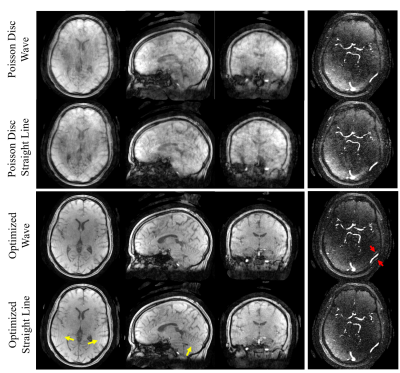

Shown in Figure 5 are the magnitude and angiogram images of the volunteer scan. There are more aliasing artifacts in the images acquired without wave, as the yellow arrows point out; however, the angiogram acquired with wave trajectory shows aliased vessels (red arrow), which may be attributed to gradient delays.

Figure 5. Applications to 4D-Flow: magnitude and angiogram images generated from optimized trajectories and the initial poisson disc trajectories. Optimized wave trajectory was able to suppress aliasing (yellow arrows in the straight line readout images). However, aliased vessels (red arrow) arise, which could be due to gradient delay. All scans were acquired with 5440 PEs, 0.86mm isotropic resolution, image matrix size=256x256x256, and the scan time was 3.5min. The images were reconstructed with PILS.